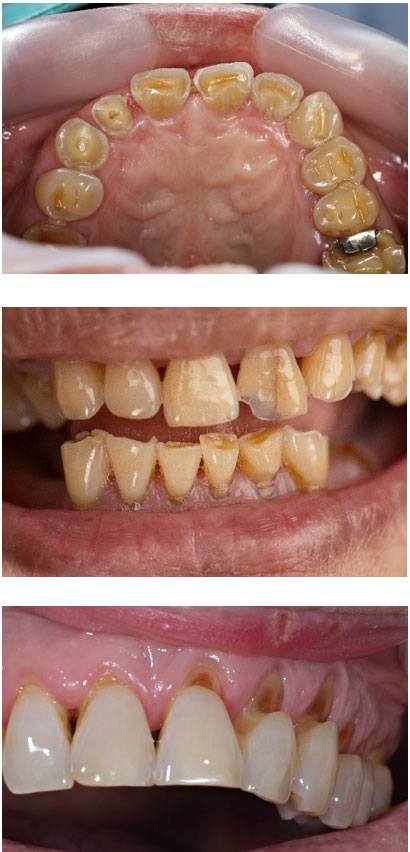

If your teeth appear shorter, flatter, or have worn-down occlusal cusps, you may already be experiencing occlusal trauma. Other warning signs include chipping or fracturing of teeth and restorative work such as fillings, veneers, or crowns. These are not merely cosmetic issues—they indicate that applied forces generated between the upper and lower dentition exceed the tolerance of tooth tissues. When these excessive forces surpass the enamel’s ability to withstand pressure, microfractures, chipping, and accelerated wear occur.

Occlusal wear is a significant clinical phenomenon that affects many individuals, often without them even realizing it. It refers to the gradual loss of tooth structure caused by mechanical forces during biting and chewing. While wear is a normal part of the aging process, it becomes problematic when accelerated by factors such as traumatic occlusal forces. One of the leading causes of these forces is an unstable stomatognathic system — the complex network of muscles, joints, and teeth that work together to facilitate chewing, swallowing, and speaking.

In an unstable system, these disbalanced movements lead to traumatic occlusal contacts — points where teeth hit inappropriately, applying undue pressure on certain areas. This can result in wear on the tooth surfaces and, over time, the breakdown of enamel, which is the tooth’s protective outer layer.

The Impact of Occlusal Wear

The consequences of occlusal wear are far-reaching. While wear on teeth might seem like a minor cosmetic issue at first, it can lead to a range of oral health problems, including:

• Tooth sensitivity: As enamel wears down, the underlying dentin becomes exposed, leading to heightened sensitivity to temperature and pressure.

• Increased risk of cavities: Thinning enamel makes teeth more susceptible to decay and cavities.

• Damage to dental restorations: Existing fillings, crowns, or veneers can be damaged or worn away by excessive occlusal forces.